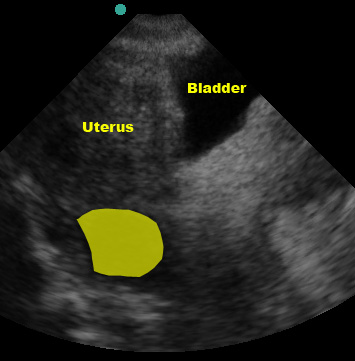

Urine in the bladder makes evaluating the pelvis much easier. Although we’ve gotten away from the days of the old ATLS mantra “a finger and a tube in every orifice,” it’s still pretty common for trauma patients to get a foley catheter. If you can, try to get pelvic images before the catheter is placed. To image the pelvis, place the probe on the abdominal midline just superior to the pubic symphysis with the US probe indicator marker to the patient’s right. If the bladder is not immediately visible (it usually is in most “2 beer” trauma patients), be sure you’re right against the symphysis and then aim the beam into the pelvis by angling the transducer to point more toward the patient’s feet. The bladder is usually easily identifiable due to the anechoic urine it contains.

(Figure 40/40.1)

Once you’ve found it, sweep caudad/cephalad to view the entire bladder. Now rotate the probe 90o clockwise so the US probe marker is now pointing towards the head and repeat the scan in a sagittal plane, sweeping left to right.

In females, fluid will initially collect in the pouch of Douglas, posterior to the uterus, NOT between the bladder and uterus. If there is a large volume of fluid, the pouch of Douglas can “overflow” and you may see fluid between the bladder and uterus.

(Figure 43/43.1)

(Figure 44)